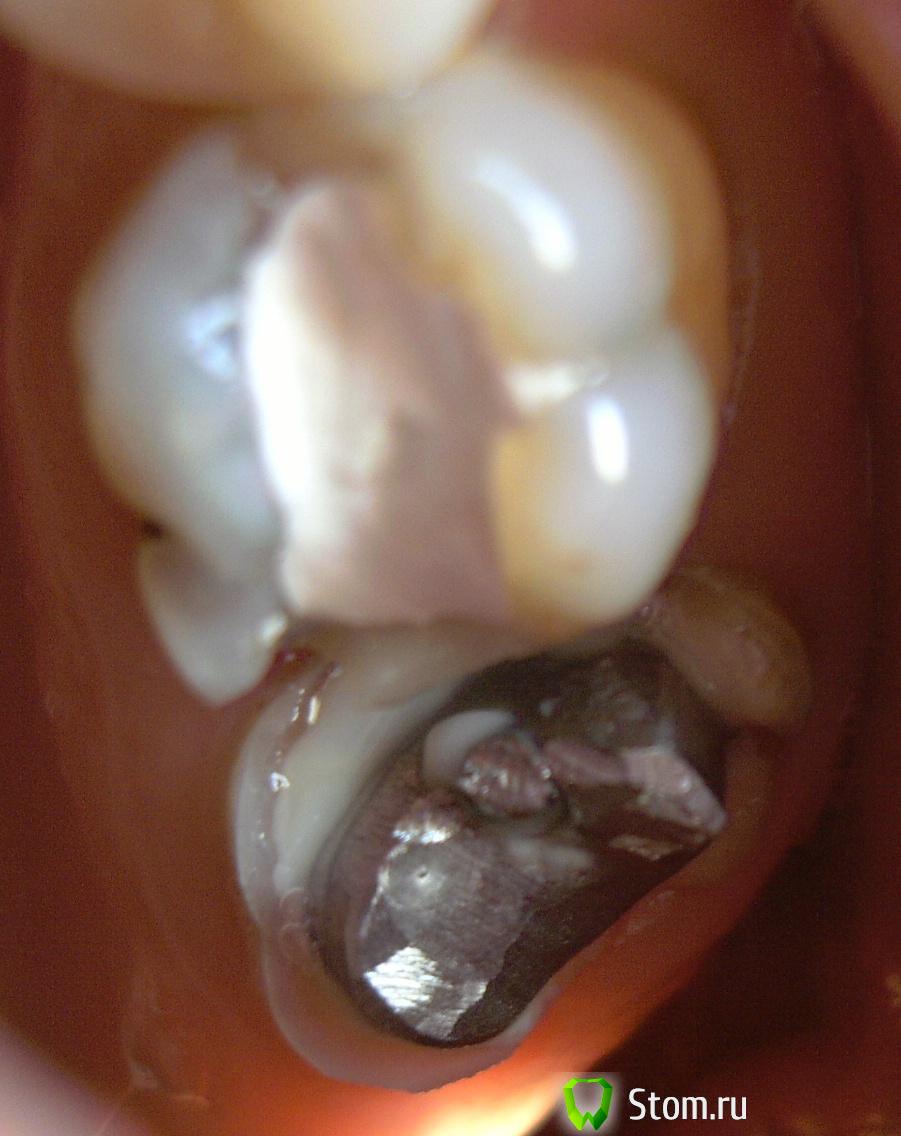

mur-in-law Опубликовано 6 февраля, 2012 Поделиться Опубликовано 6 февраля, 2012 (изменено) Здравствуйте, уважаемые доктора!Сразу к делу. У меня вот такие два верхних моляра (семерка и шестерка).На семерке, как мы видим, стоит металлическая ВКВ. Такую же я хотел бы и на соседней шестерке. А сверху мечтаю накрыть их цельнометаллическими коронками.В шестерке сейчас после мех. и мед. обработке каналов заложено лекарство в корни.Лечащий врач настаивает на том, что ВКВ ставить не целесообразно, так как придется много удалять зубной ткани. Посоветуйте мне пожалуйста, настаивать ли на ВКВ + коронка или действительно лучше обойтись СВШ + коронка, а то и просто поставить композитную пломбу.Керамическую вкладку не рассматриваю, так как это скорее всего дорого.Пломбу ставить уж точно не хотелось бы, так как не хочу рисковать, что "полетит" через несколько лет какая-нибудь стенка и придется опять ремонтировать. Изменено 6 февраля, 2012 пользователем mur-in-law Ссылка на комментарий

mur-in-law Опубликовано 22 февраля, 2012 Автор Поделиться Опубликовано 22 февраля, 2012 2. Пломба + СВШ.4. СВШ + коронка.Какой же мне лучше выбрать? Неужели так никто и не посоветует?Положился целиком и полностью на волю врача и получил: пломба на анкерном штифту+коронка. Правда коронку еще не поставили. Вообщем вотИ теперь меня, конечно, интересует, какая коронка должна больше простоять: на семерке (на ВКВ) или на этой шестерке? Коронки будут делать из хромо-никелевого сплава.И еще вопрос. Как их лучше сделать раздельно или объединить? Ссылка на комментарий